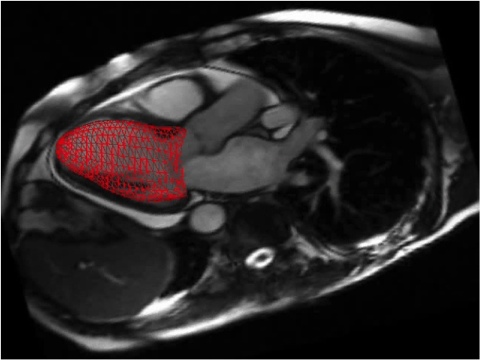

Eine MRT des Herzens kann die Funktion der Herzkammern sehr genau vermessen.Andere Untersuchungsverfahren sind an bestimmte Blickwinkel gebunden. Die Echokardiographie kann z.B. nur von einigen Punkten von der Brustwand aus Bilder des Herzens erstellen. Ein großer Vorteil der MRT ist die Möglichkeit, Bilder des Körpers aus jeder beliebigen Blickrichtung zu erstellen. Quer, schräg, gerade, 3D … Außerdem kann eine Kernspintomographie verschiedene Gewebe (z.B. Muskel, Fett, Blut, Knochen) sehr gut unterscheiden.

Narben (hier ein Herzinfarkt) lassen sich mit der Kernspintomographie des Herzens exzellent erkennen.Eine besonders herausragende Fähigkeit der MRT des Herzens ist die Erkennung von Narbengewebe. Ein Herzinfarkt ist eine der häufigsten Ursachen für die Entstehung einer solchen Narbe.  Die Größe und das Ausmaß eines Herzinfarktes sind entscheidende Faktoren für die Prognose einer solchen Erkrankung. Zu weiteren Krankheiten, die zu narbigen Veränderungen im Herzmuskel führen, gehören z.B. Herzmuskelentzündungen, aber auch seltener Stoffwechselstörungen. Die Kernspintomographie des Herzens ist die beste diagnostische Möglichkeit, Narbengewebe des Herzmuskels zu erkennen und zu beurteilen.